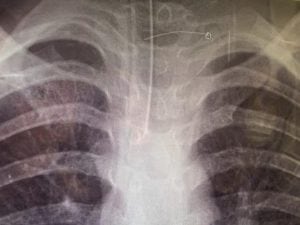

Trasportata in un ospedale nel Nuovo Galles del Sud, la bimba australiana era completamente disorientata e addirittura non riconosceva genitori e parenti. I medici hanno scoperto che l’oggetto estraneo ingoiato col panino aveva causato ascessi cerebrali.